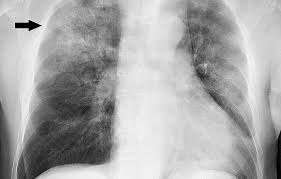

O Derrame Pleural consiste na presença de líquido na cavidade pleural. Ele é caracterizado no exame físico...